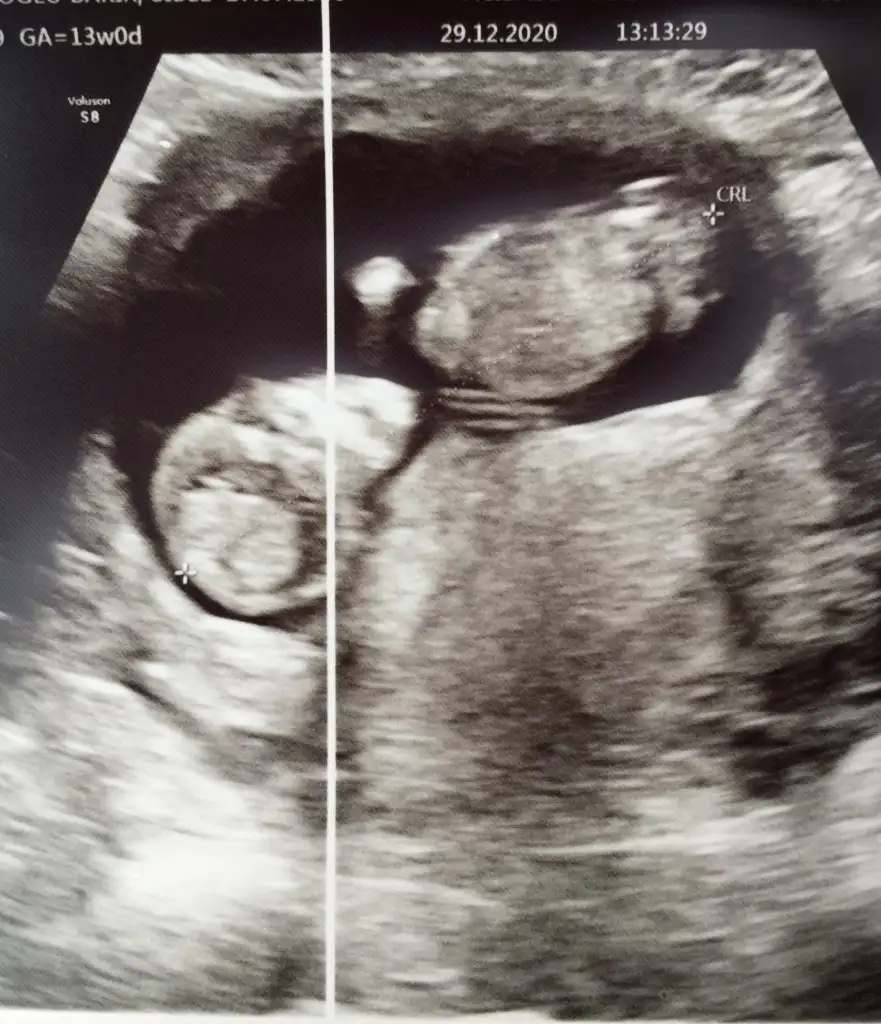

11+3 aslında ama 13te gidersem yine atarım canım 7. Haftaya kız demiştin hadi bakalım sağlıklı akıllı bebisler olsunlar da inşallahBebek baş aşağı yorum nasıl yapacam şaşırdım11 12 13 haftalar olursa paylaşın erkek gibi sanki bir uzantı var nubunda ama olmayabilir

Erkek görünüyorEki Görüntüle 2749723 Eki Görüntüle 2749724 Günaydın ikra meyra buna da bakarmısın 11+3

Başka USG varsa paylaşın nubu net degil

Yok maalesef doktorum bunları verdiBaşka USG varsa paylaşın nubu net degil